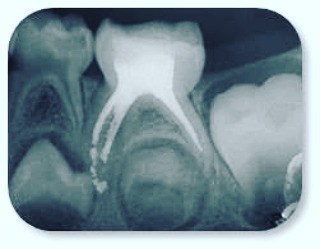

TRATAMENTO DE CANAL EM DENTES DECÍDUOS (Dente de Leite)

Muitos papais e mamães ficam espantados ao descobrir que os pequenos também passam por esse tipo de procedimento. Esse procedimento pode ocorrer, na maioria dos casos, por problemas de cáries extensa ou a um trauma, como quedas. O acesso aos condutos e a limpeza dos canais radiculares é bem semelhante do procedimento feito em adultos. O que difere é a instrumentação e finalização.